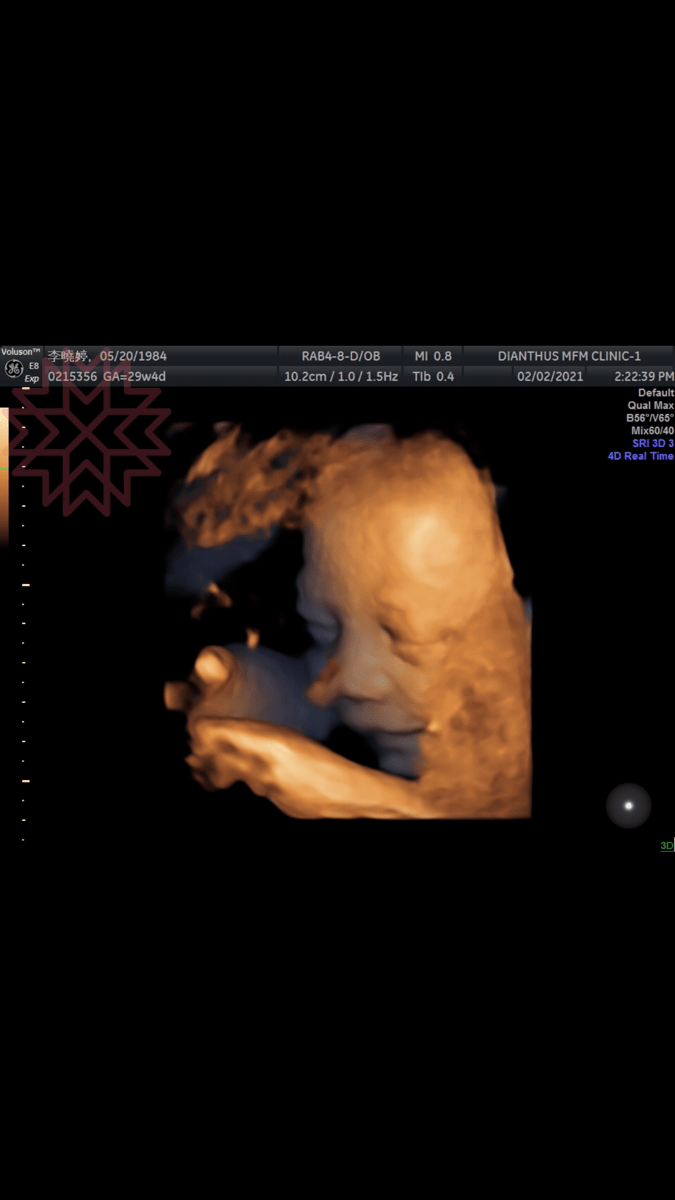

藍天~30週-32週紀錄

24 二月, 202119 一月, 2026 Roselly5發表留言

兒子阿,你知道媽咪身體除了賀爾蒙導致恥骨聯合痛、坐骨神經痛以外,還有什麼讓媽咪覺得不舒服的嗎?

發表在 10月懷胎,愛的每一天 中已加上的標籤 30週,31週,32週,胎動,lance,取名,懷孕